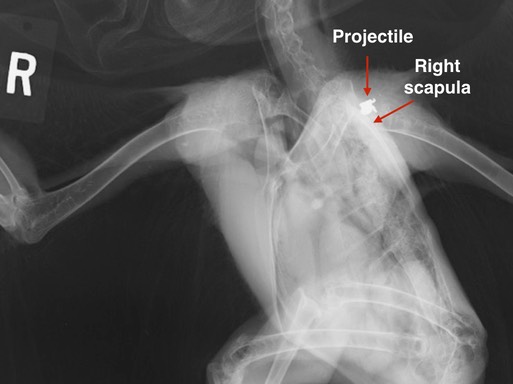

I’m hoping Red-tailed Hawk 18-763 will be the last gunshot case of the year. The hawk had a small amount of blood on his right wing, and my first thought was that he had been electrocuted. A physical exam revealed a fractured right humerus, and what felt like an old fracture of the right scapula. Radiographs told a different story, the hawk had been shot. We were palpating a lead projectile, not a fracture.

In order to better evaluate the scapula, we took a second radiograph, a lateral oblique. Intern Lahari watched closely as the hawk was positioned on his right side with the right wing pulled backwards and the left wing pulled forward, rotating his body and exposing the right scapula. Fortunately, the scapula does not appear to be damaged. (In case you are wondering why no one is wearing a lead apron, it's because we all step out of the room when the x-ray is taken. The bird is anesthetized and held in position with masking tape.)